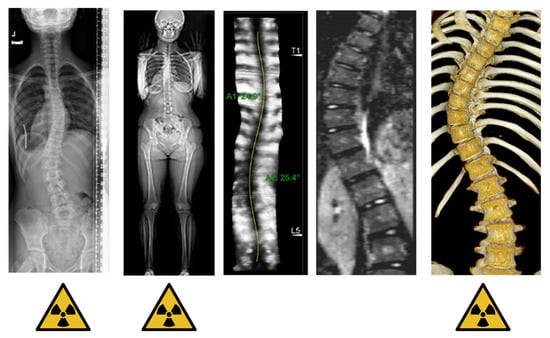

2.1. Radiography

2.2. Biplanar Stereo-Radiography

2.3. CT

2.4. MRI

| Radiography | Low | Planar evaluation of rib deformity. | Low | Evaluation of scoliosis severity and progression during follow-up. |

| Biplanar stereo-radiography | Ultra-Low | Deformity evaluation of the bone structures. Possibility for 3D reconstruction. | Low | Evaluation of scoliosis severity and progression during follow-up. |

| CT | High | High accuracy of rib cage and internal organ structures. Possibility for 3D reconstructions and automatic segmentation. | High | Sometimes used for visualizing complex osseous abnormalities, for preoperative planning or as input for spinal navigation surgery. |

| MRI | None | Mainly used to assess soft tissue rather than bone structures. | High | Evaluation for abnormalities of the spinal cord. |